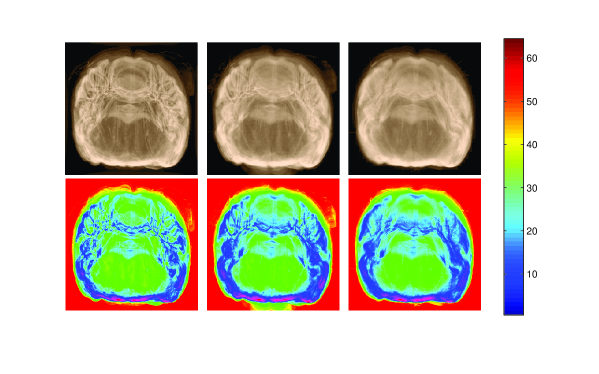

SDMs for the reconstructed volume for rigid, affine and LAGS are shown in Figure 3, both in gray scale and spectrum format. Although the volume reconstructed by successive affine registrations is smoother than the volume reconstructed by successive rigid registrations, it includes the ”banana-shape” effect which can be corrected by superimposing MRI of the rat brain (if available) on the reconstructed volume. Among three methods, the smoothest reconstructed volume is obtained by the proposed method shown in the last SDM in Figure 3.